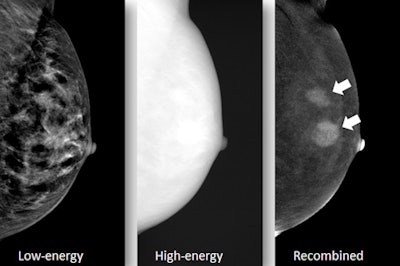

Compared with conventional mammography alone, contrast-enhanced spectral mammography (CESM) catches an additional 7.7% of lesions in recalled women -- and most of these lesions are malignant, Dutch researchers found. The low risks of using CESM as a workup tool make it a valuable addition to breast cancer care, they added.

In this study, more than 800 women recalled from breast cancer screening underwent CESM at follow-up. An experienced breast radiologist reviewed all the exams and identified malignant cases. The research team from the radiology department at Maastricht University Medical Center in the Netherlands spotted 70 lesions detected only by CESM.

From December 2012 to December 2015, 839 recalled women underwent CESM in which five minor adverse contrast reactions were observed. Median radiation dose per exam was 6.0 mGy (0.9 mGy to 23.4 mGy). The researchers identified 65 patients with 70 CESM-detected lesions, of which 54.3% (38) proved to be malignant -- most frequently invasive ductal carcinomas. The remaining CESM-detected lesions were benign, predominantly fibroadenomas.

No complications occurred during the biopsies of these lesions. Retrospectively, the majority of the lesions were either occult or a "minimal sign" on low-energy CESM images or the screening mammogram, according to the researchers.

"Our lesion conspicuity analysis showed that the majority of CESM-only lesions were, in retrospect, occult or visible as 'minimal sign,' meaning they did not raise any concerns on conventional mammographic images but became suspicious by their ability to enhance after contrast administration," they wrote.

Also, a greater proportion of CESM-detected lesions were visible on the low-energy images than on full-field digital mammography (FFDM), implying that the low-energy images show improved lesion detection compared with FFDM. This was presumably caused by the very small amount of iodine contrast already in the breast lesion when acquiring the low-energy images, they added.